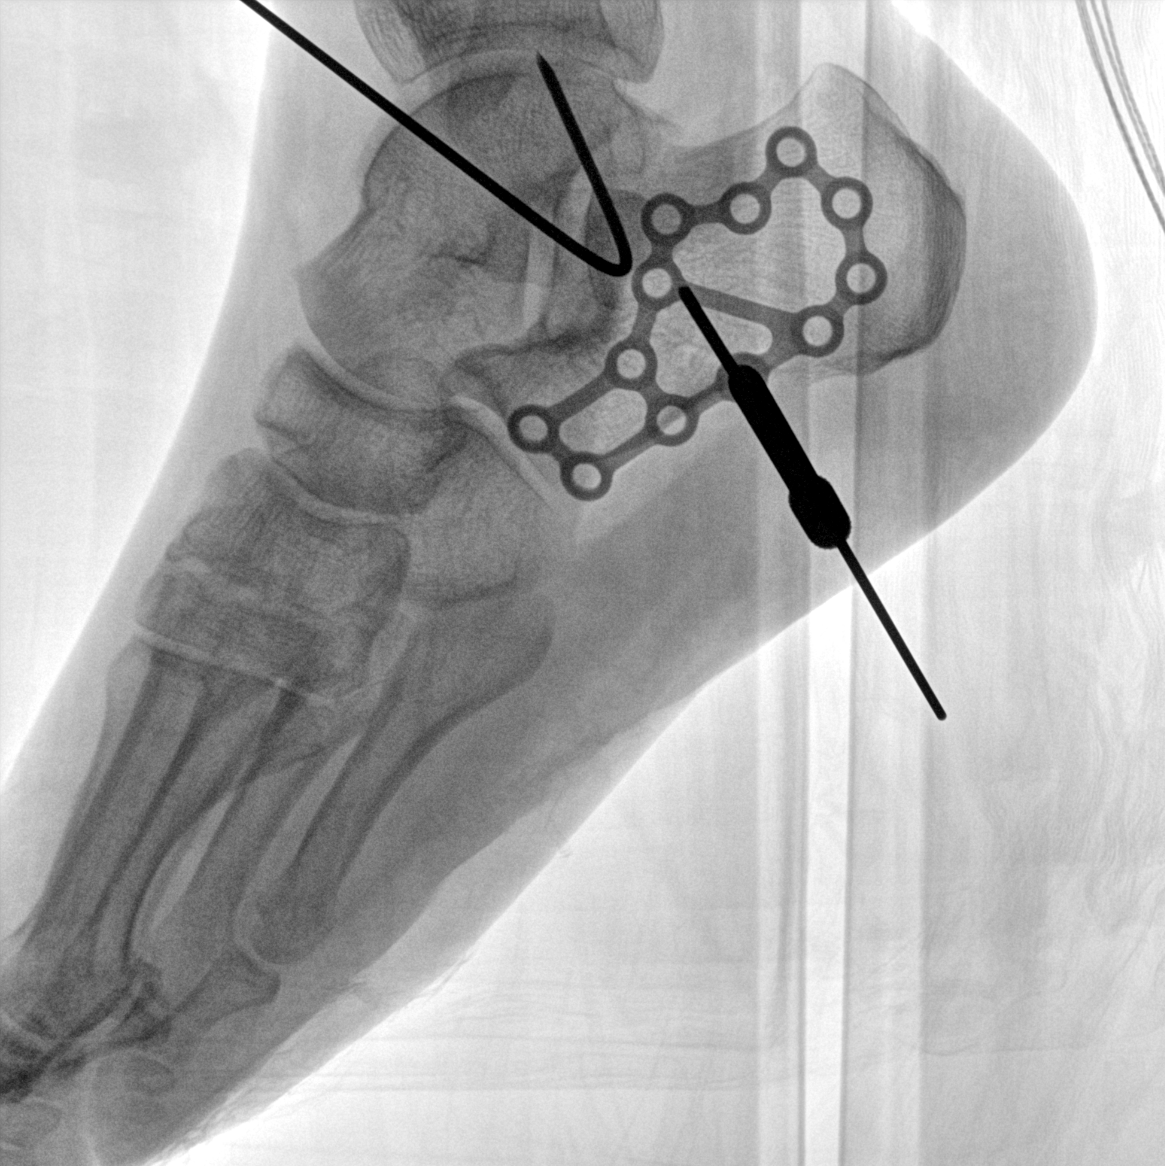

術(shù)中三維成像和橫斷面圖像提供多角度的手術(shù)診斷信息,輔助醫(yī)生進(jìn)行術(shù)中評估判斷,諸如骨折復(fù)位情況和內(nèi)植入螺釘?shù)某叽绾臀恢茫o助手術(shù)更好地完成。

在C臂掃描過程中,始終保持拍攝主體處于射線束的中心,避免了序列圖像采集過程中的橫縱方向運動,減少相對運動造成的運動偽影。